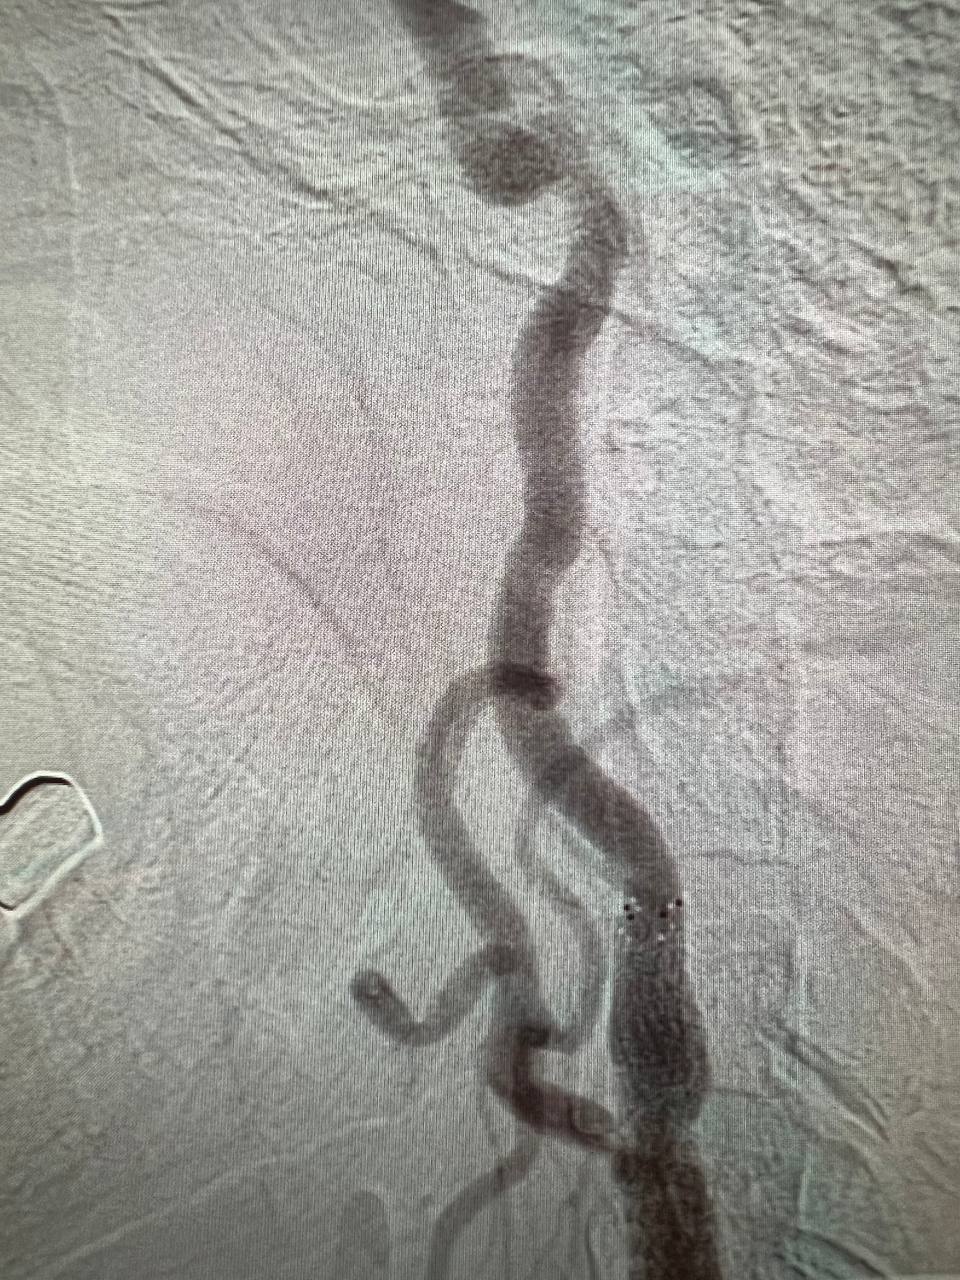

На ангіографічній системі Infinix 2011 року випуску вперше в історії госпіталя провели ургентне стентування та балонну ангіопластику лівої внутрішньої сонної артерії.

У відділення неврології поступив пацієнт з повторним ішемічним атеротромботичним інсультом в басейні лівої СМА  з елементами моторної афазії. Атеросклеротична субоклюзія (85%) С1 сегменту лівої внутрішньої сонної артерії. Дисліпідемія. Гіпертонічна хвороба ІІІ ст., 3 ст., ризик 4.

Терміново проведено ургентне оперативне втручання: ендоваскулярне стентування стенотичного ураження гирла С1 сегменту лівої внутрішньої сонної артерії. Селективна церебральна ангіографія. Це була дуже складна операція, але пройшла успішно. Відкрили ЛВСА на 90%.

Результати дослідження до та після ургентного оперативного втручання: